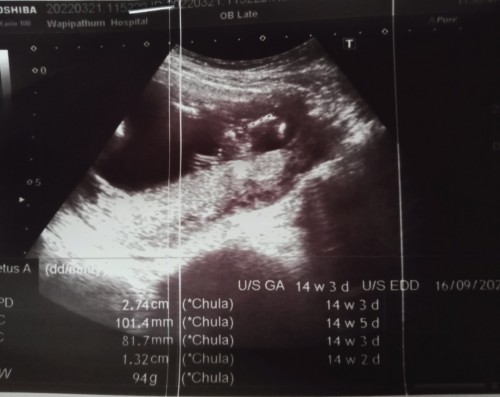

14 วีคคะ

Post reply image